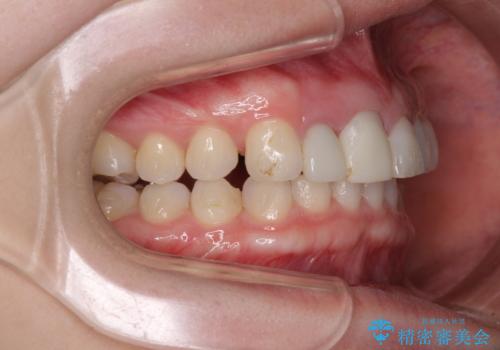

その後、他院で気になる前歯をセラミッククラウンで補綴治療をしたそうですが、やはり歯列を整えたいとのことで再度来院されました。

クラウンの状態は、根管治療の状態も含めて決して良い状態とは言えず、矯正治療後の根管治療と補綴治療の再治療を前提として、インビザラインによる矯正治療を行うこととしました。

矯正治療中に前歯2本のクラウンは外れてしまい、途中仮歯に替える必要があったので期間は掛かりましたが、歯列も整い、負担のかからない咬み合わせを達成することができました。